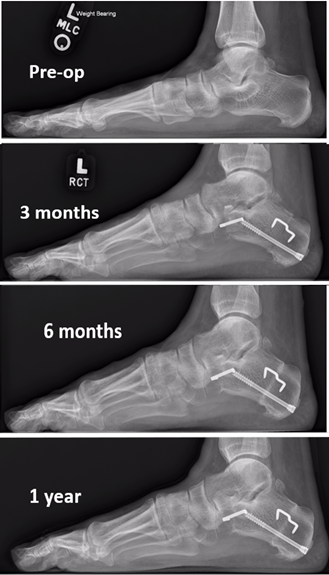

The post-operative course was uneventful with transition to partial weight-bearing at 6 weeks and full weight-bearing at 3 months, both in a CAM boot. Serial weight-bearing radiographs took place postoperatively at 3 months, 6 months, and 1 year. We evaluated the sagittal plane position of the first ray by measuring the angle of the bisection of the talus and the first metatarsal (ie, Meary’s angle5), the distance from the dorsal cortex of the first metatarsal to the dorsal cortex of the second metatarsal (ie, Seiberg’s index5), and the distance from the dorsal cortex of the first metatarsal 10mm proximal to the articular surface to the weight-bearing surface (see table below). Measurements at the 3-month follow-up were compared to the 6- and 12-month radiographs to observe any dynamic change. From the 3-month to the 12-month follow-up, there was a 0.7-degree change in Meary’s angle, a 1.8mm decrease of Seiberg’s index, and 8.3mm of correction of the first metatarsal to the weight-bearing surface.

In the case study presented above, dynamic correction of the first ray occurred over the course of one year after flexible flatfoot correction without the addition of a Cotton osteotomy. There was 1.8mm of correction of Seiberg’s index and 8.3mm of correction of the first metatarsal height to the weight-bearing surface. There was no obvious change seen in Meary’s angle over the post-operative period. There was a change from the pre-operative X-ray to the 3-month x-ray, but this is a well-known and documented benefit of the Evans osteotomy. However, two of the three metrics evaluated appear to indicate that there is potentially a change in mechanical forces resulting in plantarflexion of the first ray post-operatively. It is the opinion of these authors that the correction observed is a result of the increased mechanical advantage provided to the peroneus longus muscle after the lateral column is lengthened.

The case study presented demonstrates a change in first metatarsal position during the postop weight-bearing period after an Evans osteotomy. We attribute this change to the increased mechanical advantage provided to the peroneus longus as a result of the lateral column lengthening procedure. Our hope is to stimulate debate on whether inclusion of a Cotton osteotomy is necessary to produce the desired correction of a flexible forefoot varus. Further research is required to further assess dynamic forefoot varus correction that can occur after an Evans osteotomy in patients with known flexible forefoot varus.